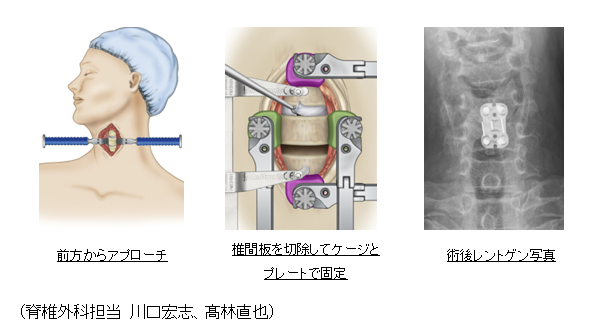

頸椎前方除圧固定術(Anterior Cervical Discectomy and Fusion:ACDF)

適応:頚椎症性脊髄症、頚椎椎間板ヘルニア

頚椎症性脊髄症、頚椎椎間板ヘルニアで1〜2箇所の病変がある場合や、頚椎のアライメント(並び)が後弯している方などに適応されます。頚部前方に約4cmの皮膚切開を加え、顕微鏡を用いて椎間板を切除し神経の圧迫を除去します。椎間板を切除したスペースにはケージを挿入し、プレートで固定します。術後10-14日程度で退院が可能です。